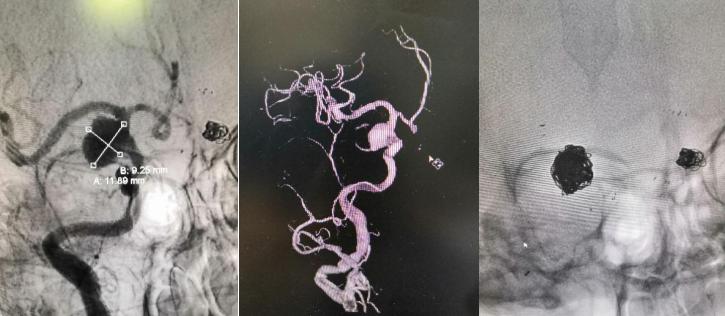

近年来西安市红会医院神经外科以本院脑卒中中心建设为契机,在别小华主任的带领下,神经外科血管内治疗团队顺利独立开展了颅内动脉瘤栓塞、脑血管畸形栓塞、颅内外动脉狭窄支架成形术、急性脑血管闭塞取栓术等血管内介入治疗,填补了我院的多项技术空白。

颅内动脉瘤单纯弹簧圈栓塞治疗

颅内动脉瘤支架辅助栓塞治疗

脑动静脉瘘栓塞治疗